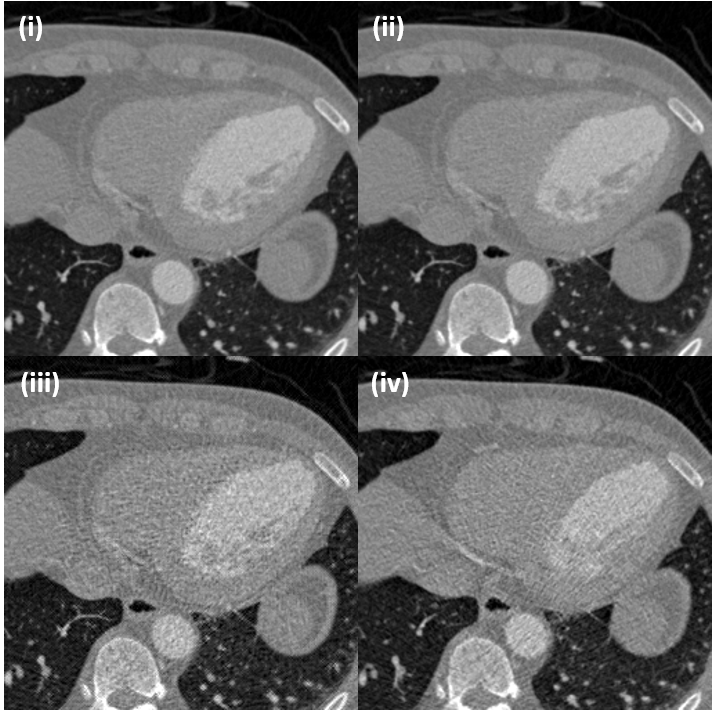

Also, Fig. 12 shows three representative denoising results by the proposed cycle-free CycleGAN with an invertible generator. The gray boxes in the low-dose inputs and denoised outputs are enlarged. The proposed method properly removes noise components from input low-dose CT images, so that each soft tissue in the resulting denoised images is distinguished clearly.